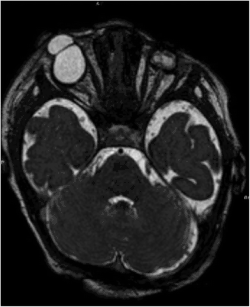

| Bilateral cryptophthalmos with microphthalmos in the left ocular globe and abnormal right ocular globe in a female infant with Fraser syndrome. | |